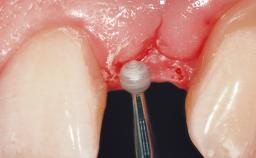

Immediate Flapless Placement of an Implant in a Maxillary Right Lateral Incisor Site

This 43-year-old male patient, a non-smoker, came to our practice because of a fracture of tooth 12 caused by a bicycle accident. Due to the combined para- and infrabony crown and root fracture, tooth extraction, and subsequent implant placement were suggested to the patient as the therapy of choice. The patient had high esthetic expectations with regard to the treatment outcome and asked for an immediate fixed provisional restoration. His individual esthetic risk profile summed up to a medium esthetic risk.

Soft Tissue Grafting None

Soft Tissue Contour and Volume Ideal